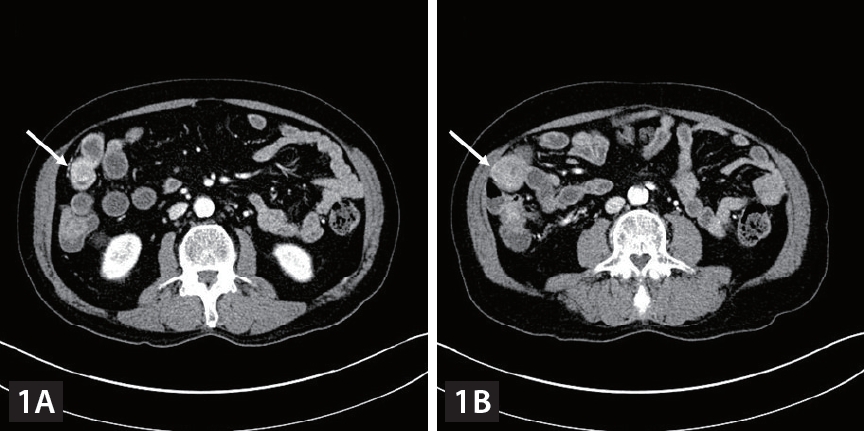

Computed tomography (CT) imaging. (A-C) Contrast-enhanced CT showed polypoid enhancing masses in the distal ileum at intussuscipiens (white arrow) and dilatation of upstream small bowel dilatation (blue arrow).

A 75-year-old man with chronic hepatitis B was diagnosed with pulmonary metastases from hepatocellular carcinoma (HCC) and was treated in order with sorafenib, regorafenib and nivolumab. However, nivolumab treatment was discontinued after the 13th administration because of poor general condition. After 2 years of conservative management, follow-up computed tomography (CT) showed no definite viable tumor in the liver and no pulmonary metastatic lesions and tumor markers were not elevated. However, iron deficiency anemia (IDA) was observed. Fecal occult blood test was negative. Although further esophagogastroduodenoscopy and colonoscopy were performed, no definite cause of the gastrointestinal (GI) bleeding was identified. While prescribing iron supplements, we performed follow-up examinations. Six months later, follow-up abdominal CT showed polypoid enhancing masses in the distal ileum (Fig. 1). There was no viable intrahepatic lesion. Laboratory results showed IDA and elevated protein induced by vitamin K absence or antagonist-II level (90.8 mAU/mL). The patient denied melena. Polypoid lesions were not detected on colonoscopy and video capsule endoscopy. Three months later, the patient visited the emergency room complaining of nausea, vomiting and abdominal pain. The AFP level was 1.9 ng/mL and PIVKA-II level was 98.7 mAU/mL. An abdominal CT scan showed polypoid enhancing masses in the distal ileum at intussuscipiens, suggesting intussusception of the ileum with a lead point (Fig. 2). Segmental small bowel resection and endto end anastomosis were performed. The histological findings were consistent with those of metastatic HCC (Fig. 3). Small bowel intussusception in adult due to metastasis from HCC is extremely rare. To date, only four cases have been reported. Two cases were diagnosed with HCC metastasis to the small bowel manifesting as intussusception, and one case was diagnosed with double-balloon enteroscopy, and the other case was diagnosed with 11C-Acetate PET/CT. Our case was a small bowel metastasis of HCC manifested as obscure-occult GI bleeding, resulting in intussusception. To our knowledge, this is the first report of HCC metastasis to the small bowel manifested as obscure-occult GI bleeding. Even if HCC metastasis to the small bowel is rare, if HCC patients exhibit obscure-occult GI bleeding symptoms, it should be considered.